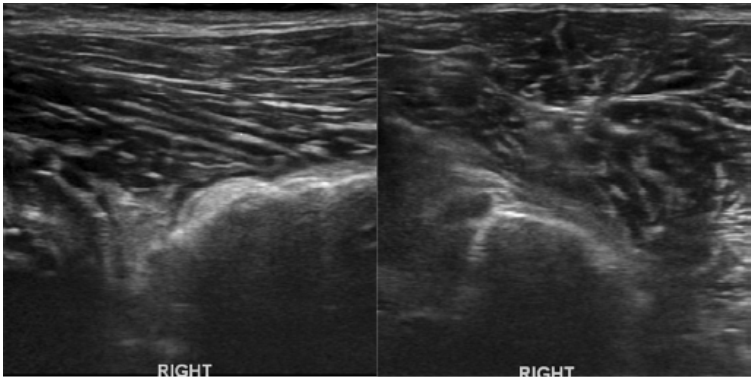

Methods: Medical records of 73 agility performance canines that underwent musculoskeletal ultrasound evaluation of bilateral iliopsoas muscle groups were retrospectively reviewed. Data included signalment, previous radiographic findings, and ultrasound findings. A 3-tier grading scheme for acute strains was used while the practitioner also evaluated for evidence of chronic injury and bursitis.

Results: The majority of pathologies were localised to the tendon of insertion, with the majority being low grade I-II strains (80.8%). Tendon fibre disruption (71.2%) and indistinct hypoechoic lesions (91.8%) were the most common of acute changes noted. Hyperechoic chronic changes were noted in 84.9 percent of cases. Acute and chronic changes were commonly seen together (62.8%).

Conclusion: Diagnostic musculoskeletal ultrasound was used to identify lesions of the iliopsoas tendon consistent with acute and chronic injury, as well as identifying the region of pathology. The majority of agility performance dogs had low grade acute strains based on the tiered system, with mixed acute and chronic lesions being noted frequently.

Application: Diagnostic musculoskeletal ultrasound provides a non-invasive diagnostic modality for patients suspected of having an iliopsoas strain.